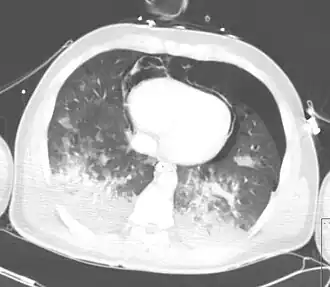

TAC mostrando neumopericardio con neumomediastino, neumotórax, hemotórax, y contusión pulmonar después de un severo traumatismo torácico | ||

Neumopericardio es una condición médica donde entra aire en la cavidad pericárdica. Esta condición ha sido reconocida en neonatos prematuros, en el que se asocia con patología pulmonar severa, después de una resucitación enérgica, o en la presencia de ventilación asistida.[1] Esta es una complicación seria, la cual si no se trata puede llevar a taponamiento cardiaco y la muerte. Una condición llamada neumomediastino la cual es la presencia de aire en el mediastino, puede imitar y también coexistir con neumopericardio.

El mecanismo responsable del neumopericardio es el Efecto Macklin – Inicialmente hay un gradiente de presión incrementado entre el alveolo y el espacio intersticial. La presión incrementada lleva a la ruptura alveolar, como consecuencia, entra aire a través del espacio pulmonar intersticial pericapilar. Este espacio es continuo con el peribronquial y las vainas perivasculares pulmonares. Desde ahí, el aire va al hilio pulmonar y luego al mediastino. En caso de rasgadura pericardial, este aire penetra la cavidad pericardial y el neumopericardio se desarrolla. La condición puede mantenerse asintomática o puede progresar a condiciones que amenazan la vida como neumopericardio tensional o taponamiento cardiaco.[3]